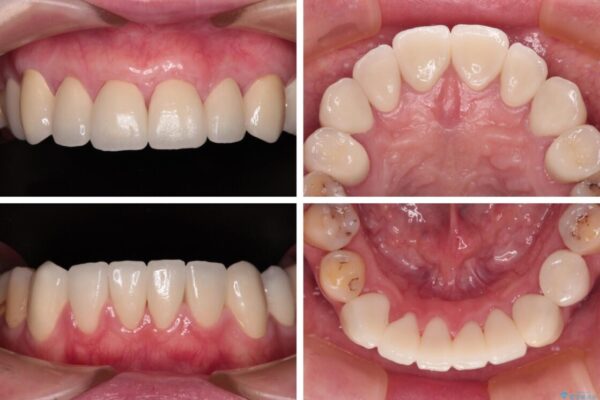

治療後

• むし歯だらけの前歯をオールセラミッククラウンできれいに 治療後画像

治療後について

歯肉移植術による根面被覆を行うかどうかは非常に悩まれていましたが、歯肉が覆われたことで長く見えていた歯の長さが整い、きれいな前歯の仕上がりとなりました。